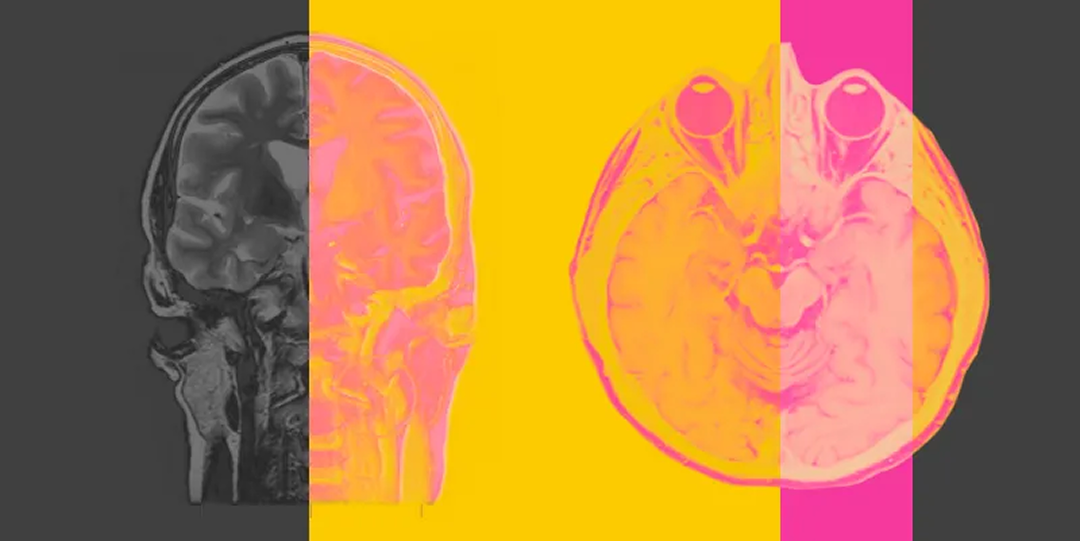

Дофамин — это гораздо больше, чем просто «гормон счастья»: он помогает нам двигаться, учиться, а ещё выбирать и действовать.